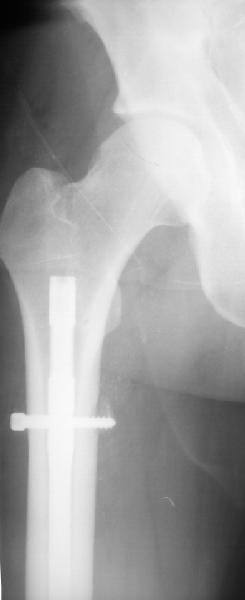

В целом возражений нет, кроме как по предствленному снимку сложно судить о месте введения гвоздя, если через грушевидную ямку или в её районе, то все-таки риск повреждения медиальной огибающей артерии присутствует и кажется Джолдас приводил статистику о последующем развитии ав. некроза головки бедра при антеградном штифтовании через этот порт.

Если как на приложенной картинке - мало места?